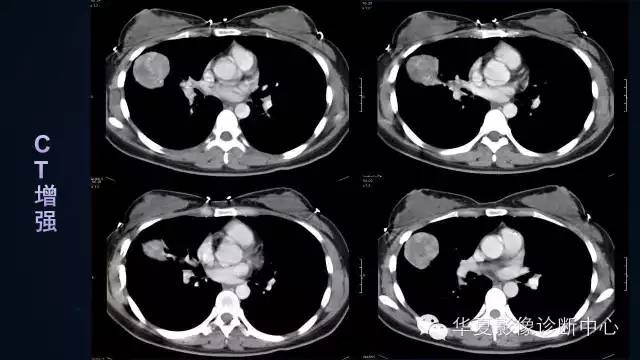

【病例】肺肉瘤样癌1例CT影像表现